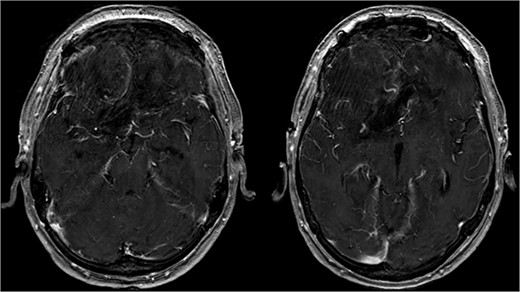

Postoperative cMRI showed typical postoperative changes with no residual tumor tissue (Fig. 4), prompting initiation of extubation and weaning. Histopathological analysis confirmed a meningothelial meningioma (WHO grade I) (Fig. 5) with no indication for further treatment. Discharge occurred after 12 days, with subsequent 6-month follow-up revealing no recurrence and improved cognitive function.

Showing the postoperative T1-weighted MRI with no residual tumor tissue.